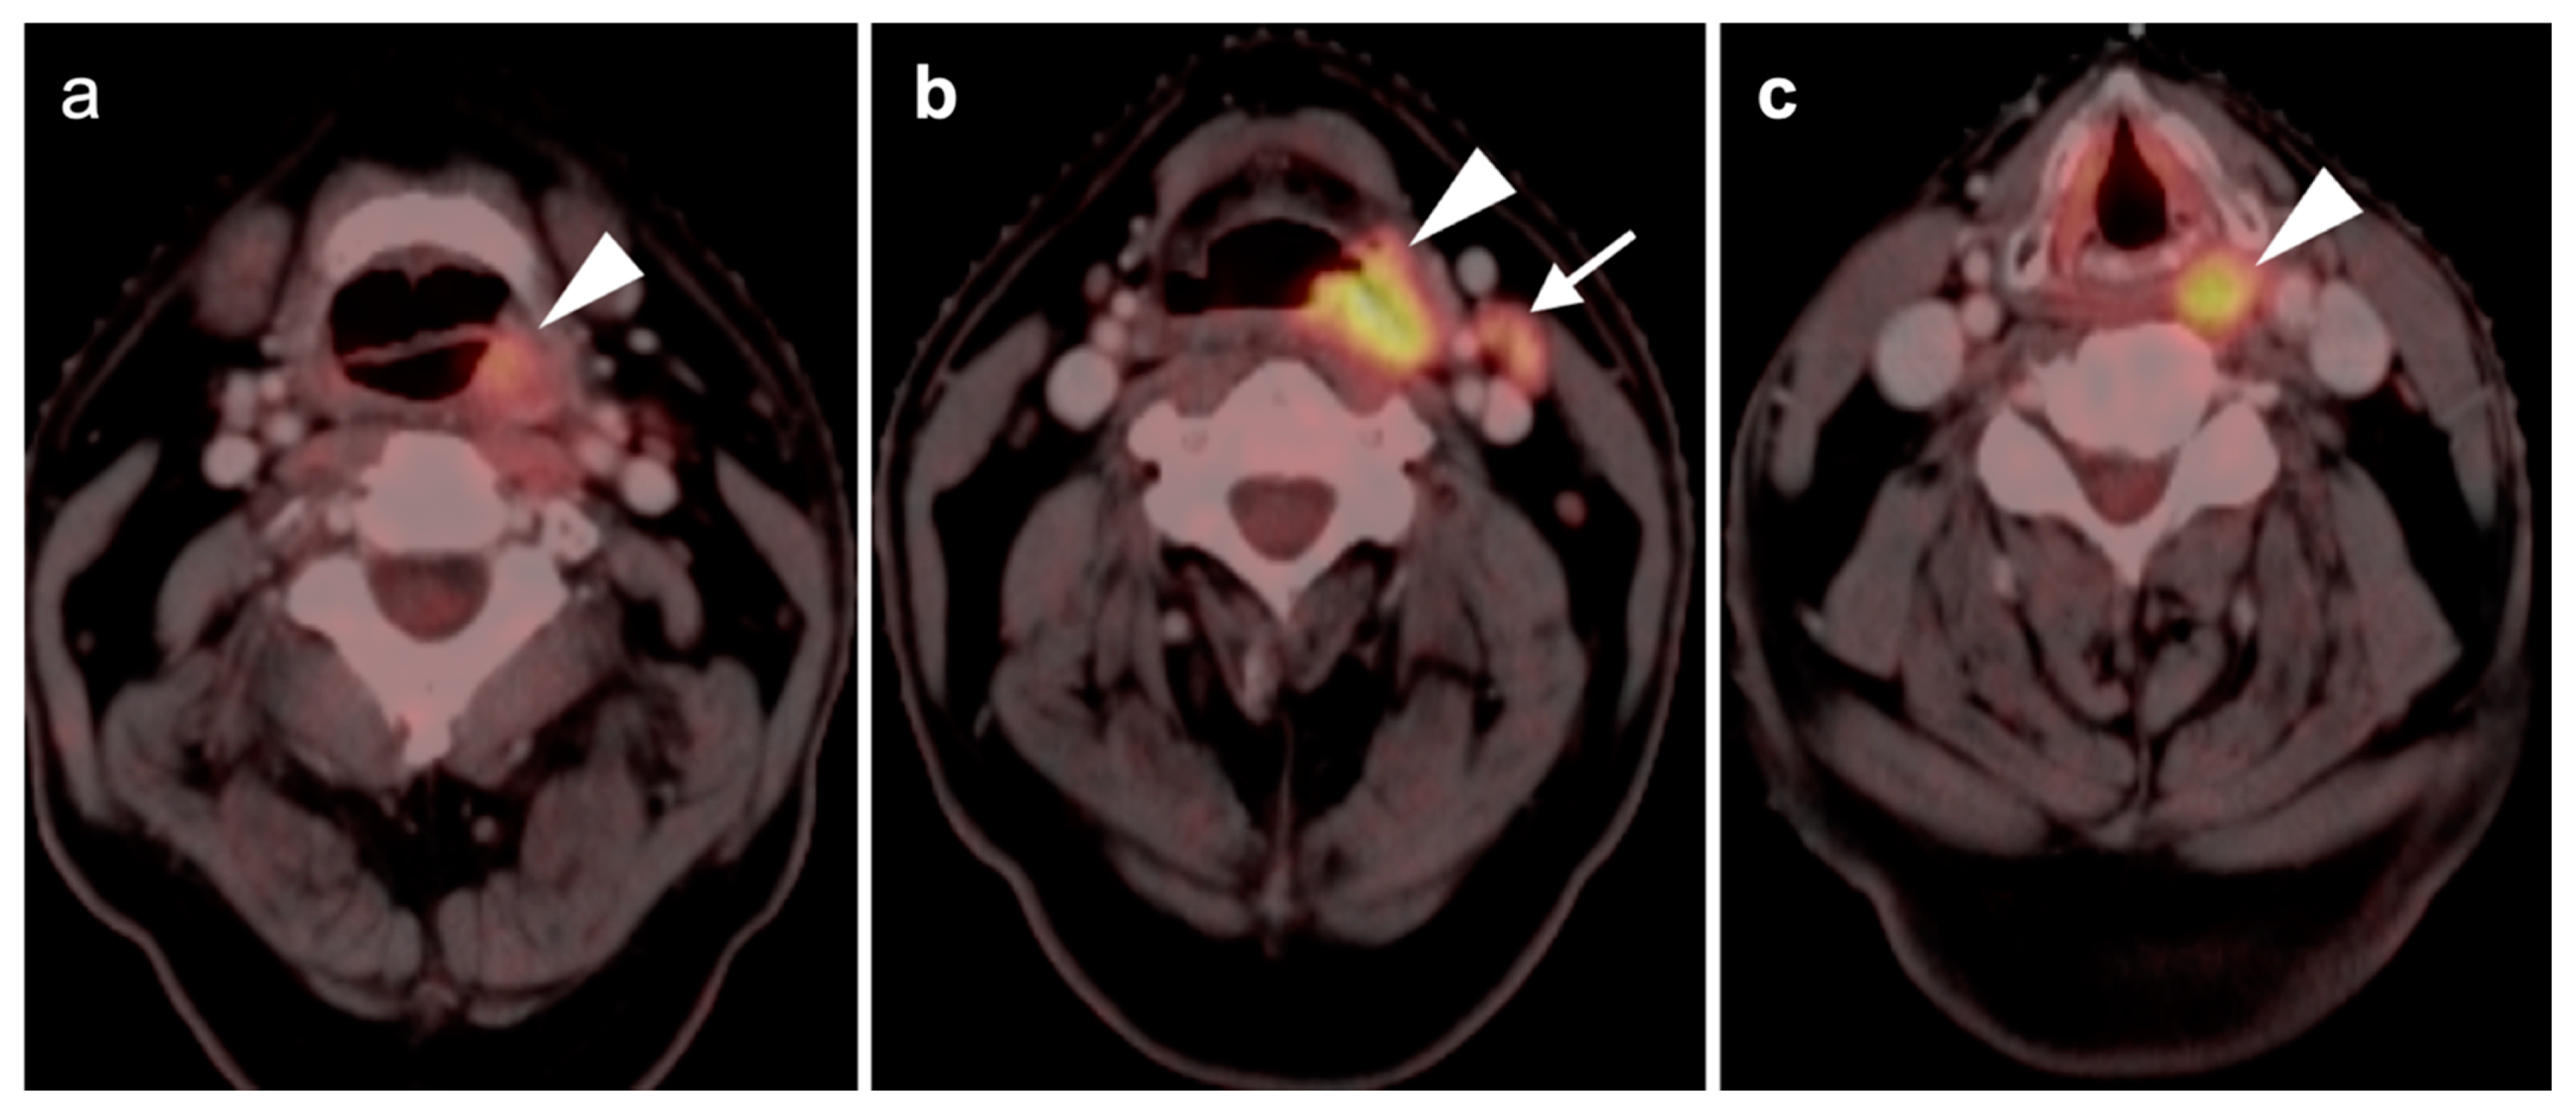

2.2. Squamous Cell Carcinoma of the Head and Neck (SCCHN)

- Oropharyngeal squamous cell carcinoma

- Laryngeal squamous cell carcinoma